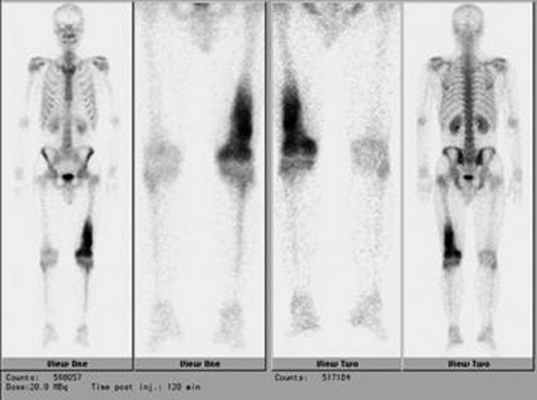

Планарная сцинтиграфия дает возможность определить распространенность опухоли по длине кости, а также выявляет отдаленные метастазы остеосаркомы в скелете (рис. 5).

Рис. 5. Радиоизотопное исследование скелета при саркомах костей